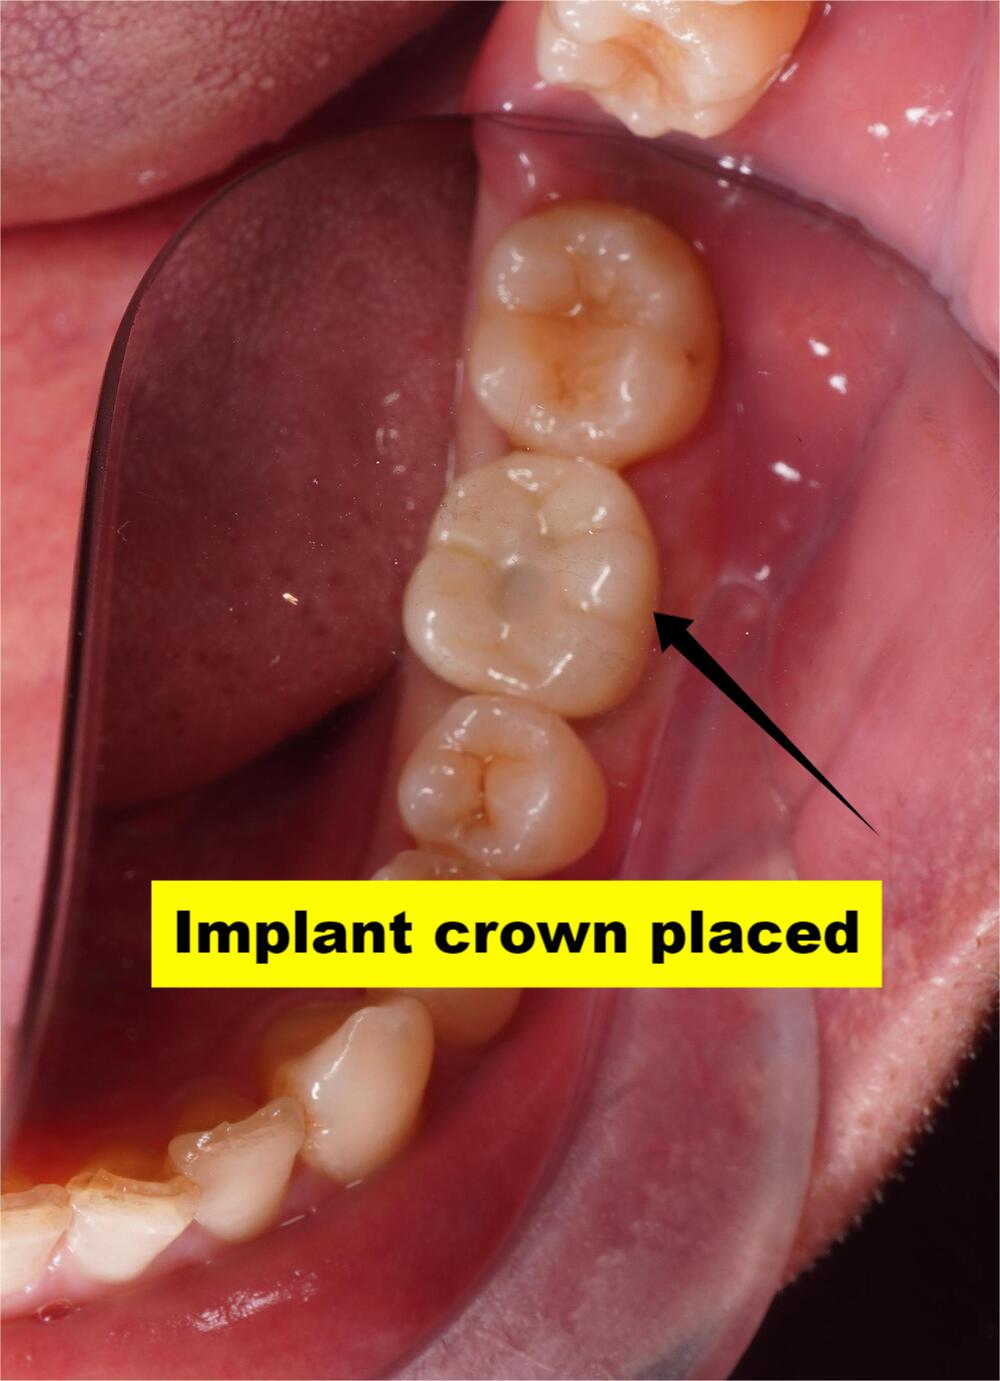

(Single Implant)

Actual patient results. Individual outcomes may vary.

Single implant

Once healed, we attach the custom crown, your new tooth that looks, feels, and functions naturally.